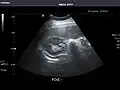

Liver -